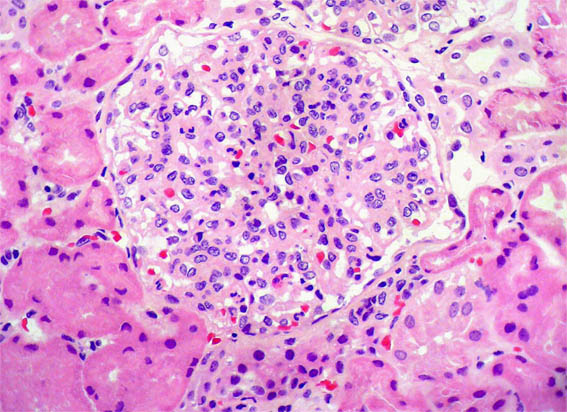

Figura 3.

H&E, X400.